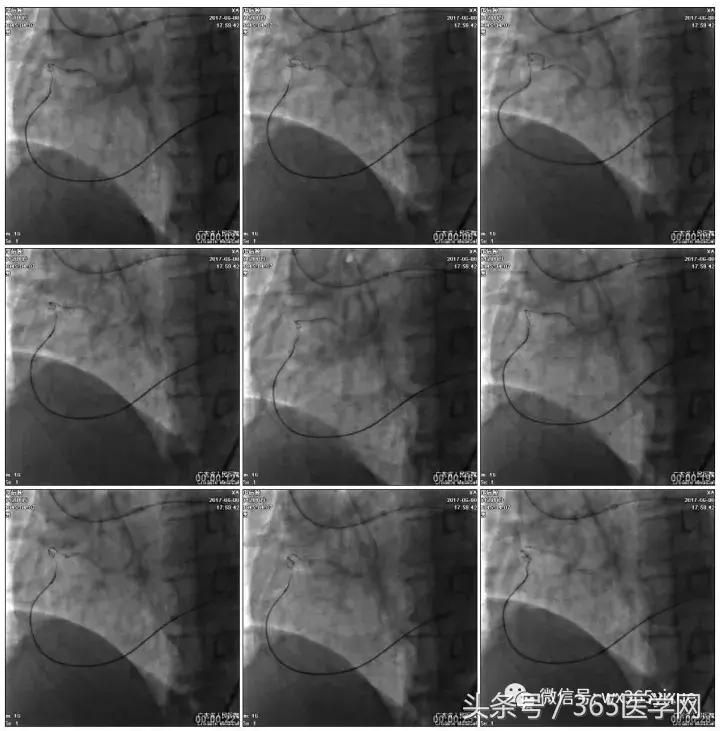

1.更换RG3导丝

2.GC送入普通导丝,保护LM

RCA闭塞段球囊扩张后IVUS

支架术后造影结果

支架术后IVUS